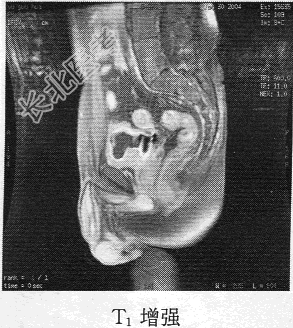

- 单项选择题患者男,76岁。反复无痛性肉眼血尿3个月, MR图像如下,最有可能诊断为

C、膀胱癌